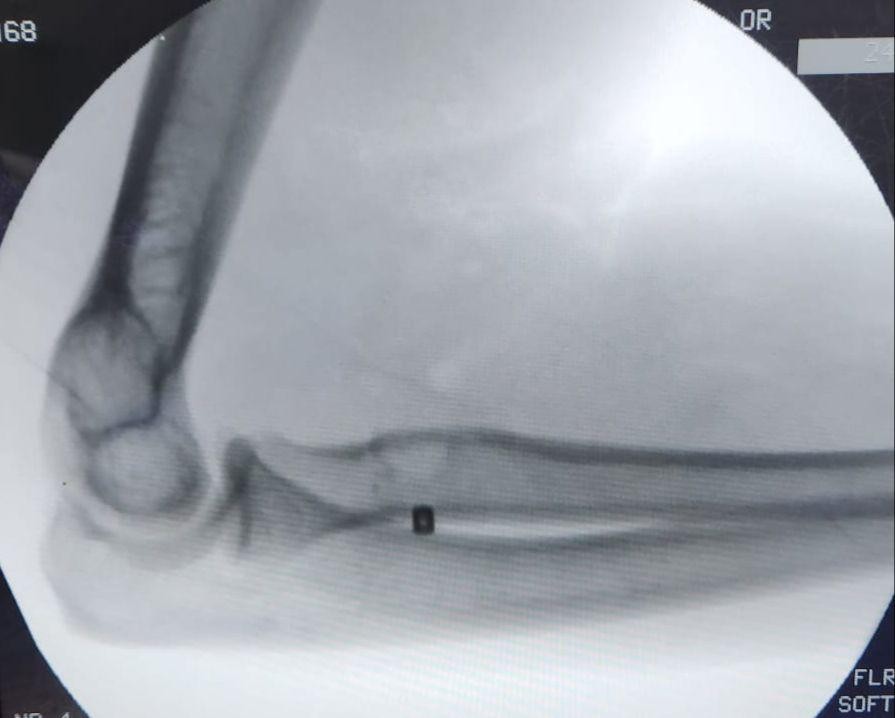

تمكن فريق طبي في جراحة العظام بمستشفى الملك فهد بجدة من إجراء عملية لمريض في الأربعين من عمره ، و إعادة وتره المقطوع ، نتيجة لتعرضه قبل شهر لقطع في العضلة التي تسمى البايسيبس ، و قد تمكن الفريق من إعادة و تثبيت الوتر المقطوع لمكانه بقيادة الدكتور شهاب بوسطجي استشاري الزمالة الألمانية في جراحة العظام و إصابة الملاعب بمستشفى الملك فهد بجدة .

و أشار الدكتور بوسطجي رئيس الفريق الطبي الذي أجرى العملية أنه قد تم إجراء الفحوصات اللازمة للمريض قبل العملية من أشعة رنين مغناطيسي ، مضيفاً إلى أن هذا النوع من العمليات يُعد نادراً و من العمليات الدقيقة جداً التي تحتاج وقتاً للعودة لوضعها الطبيعي .